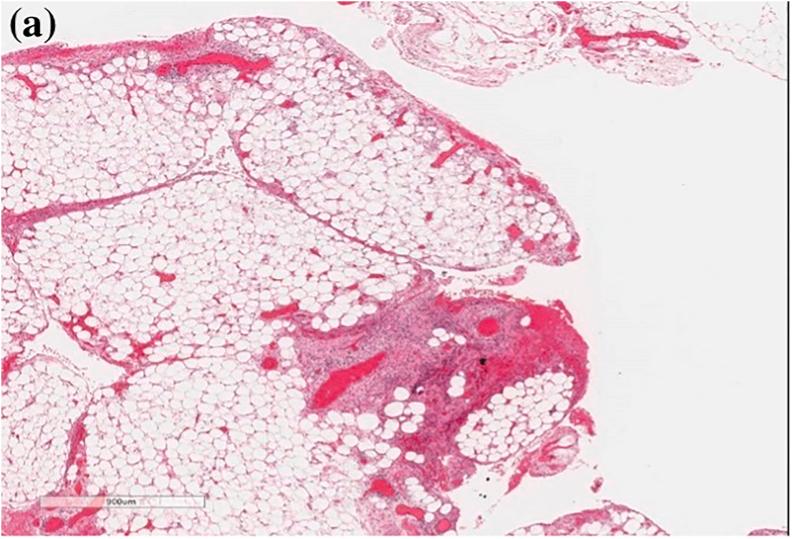

We report the first case of a primary omental pregnancy in a subseptate uterus in literature. Our patient, a 33-year-old female, G8P4+3, presented with nausea, severe abdominal pain, and vaginal spotting at 6 weeks' gestational age. She had mild tenderness below the umbilicus, with positive cervical and right adnexal tenderness. 2D-ultrasound revealed a subseptate uterus, normal ovaries and fallopian tubes, absence of a gestational sac, and a 4x3x2.5 cm mass in the right adnexa. A mini-laparotomy was performed due to suspicion of ruptured tubal pregnancy, revealing a primary omental pregnancy which was managed via partial omentectomy.

我们报告了文献中首例子宫纵隔不全合并原发性大网膜妊娠的病例。我们的患者是一名33岁女性,孕8产4 + 3,孕6周时出现恶心、严重腹痛和阴道点滴出血。她脐下有轻度压痛,宫颈和右侧附件压痛阳性。二维超声显示子宫纵隔不全,卵巢和输卵管正常,未见妊娠囊,右侧附件区有一个4×3×2.5厘米的肿块。因怀疑输卵管妊娠破裂行小切口剖腹术,发现原发性大网膜妊娠,通过部分网膜切除术进行处理。